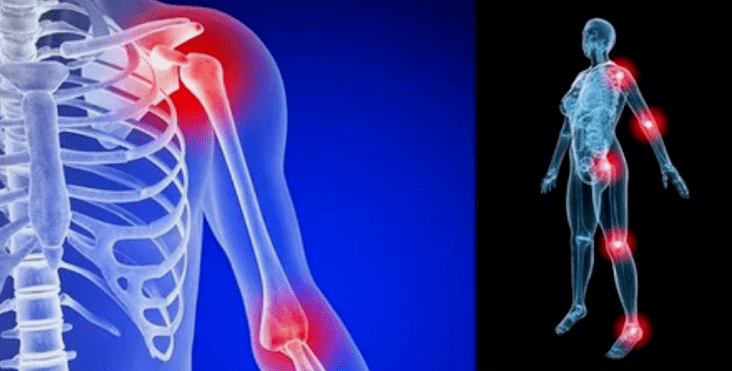

As manifestações da doença diferem pouco, dependendo da localização, mais frequentemente os sinais são refletidos nos joelhos, articulações do ombro e quadril, devido à alta carga.

Principalmente as queixas se resumem a:

- dor. Eles têm baixa gravidade no estágio inicial, com agravamento do estado de sensação intensificado. Inicialmente, as articulações doem somente depois de acordar, depois de um leve e quente, as sensações desaparecem. Com o tempo, as dores aparecem à noite, elas perturbam bastante durante e após a caminhada prolongada, correndo etc. Na última etapa, a síndrome da dor persegue uma pessoa o tempo todo;